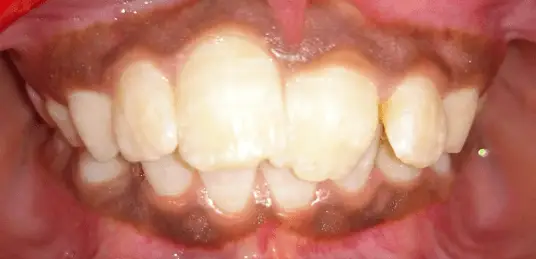

2 BY 4 APPLIANCE THERAPY

A 11 year old girl reported to the department with a complaint of irregularly placed upper front teeth. On clinical examination there was crowding in the maxillary anterior teeth and Angle’s Class I molar relation. Final diagnosis of Angle’s Class I molar relation with Dewey’s type 1 was proposed. A 2 by 4 appliance therapy was proposed in this case in which 4 MBT brackets were placed on the upper incisors and with 0.06 band material , banding was done on 16, 26 and 0.012 “ Niti wire was placed. In the first month an open coil spring was placed irt 11,21. A follow up of 6 months showed alignment of the upper anterior teeth and finally fixed lingual retainer were bonded.